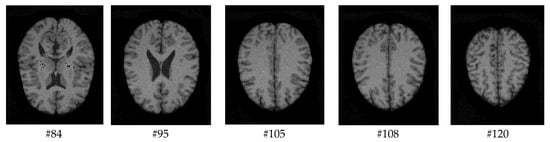

As mentioned before, the images of the first five datasets in Table 3 were used to evaluate the performance of the HMRF-WOA. Figure 1, Figure 2, Figure 3, Figure 4 and Figure 5 show some slices of a T1-weighted image (slices: 84, 95, 105, 108, 120). These brain images correspond to the slices under different types of conditions, such as database type, dimension image, noise level, intensity non-uniformity level, and slice thickness (mm). In Table 1, rows 1 to 5 summarize the parameters of Figure 1, Figure 2, Figure 3, Figure 4 and Figure 5, respectively. Figure 6 represents the ground truth segmentation of slices 84, 95, 105, 108, and 120. In this figure, each column contains the three tissues, GM, WM, and CSF, of each slice. Figure 7, Figure 8, Figure 9, Figure 10 and Figure 11 show the segmentation results, where the four tissues (BG, GM, WM, and CSF) are shown with different colors. The yellow, red, and green colors represent the segmented regions of GM, WM, and CSF, respectively. As we can also see from these figures, the resulting segmented images in Figure 7, Figure 8, Figure 9, Figure 10 and Figure 11 are almost close to the initial images in Figure 1, Figure 2, Figure 3, Figure 4 and Figure 5.

Figure 2. Slices with Noise = 3%, INU = 20% of database 2.